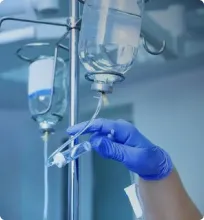

Способы лечения компьютерной игровой зависимости разрабатываются в наркологии. Этому есть объяснение. Механизм развития игромании схож с появлением зависимости от психоактивных веществ.

В некоторых случаях человеку просто достаточно бесед с психотерапевтом. В более сложных ситуациях назначается медикаментозная поддержка. При работе с психотерапевтом для успешного лечения зависимости от компьютерных игр важно добиться следующего: